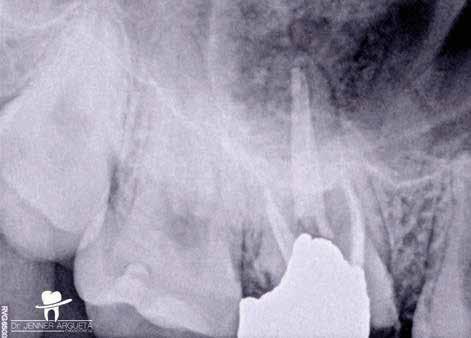

Gyökéramputációt főként a furkáció érintett nagyőrlő fogak ellátása során szoktunk alkalmazni. Derks és mtsai. vizsgálatában a gyökéramputált nagyőrlő fogak közel 80%-a 20 évvel a beavatkozás elvégzését követően is megtartott volt. 1998 októberében egy 39 éves férfi páciens a jobb alsó kvadránsban jelentkező ínyérzékenység miatt kereste fel rendelőnket. A klinikai vizsgálat során jobb alsó első és második nagyőrlő fog között (46–47) nagy kiterjedésű csontveszteséget észleltünk. Ettől eltekintve a teljes fogazat parodontális státusza megfelelőnek bizonyult. A jobb alsó kvadránsban végzett szenzibilitás vizsgálat során arra az eredménye jutottunk, hogy a 46-os fog vélelmezhetően elhalt (10. ábra).

A pácienst tájékoztattuk, hogy az endo-paro léziókkal rendelkező fogak alapvetően rossz prognózissal rendelkeznek.

A kezelés hosszú távú sikeressége nagymértékben függ a csontveszteség mértékétől, a megmaradó gyökércsonk hosszától, a gyökerek közti távolságtól, a rezekálni kívánt

gyökér görbületétől, a csontos defektus megszüntetésének sikerességétől, a fogbél állapotától, és a szükséges restauratív és szájhigiénés beavatkozások elvégzésétől.

A páciens beleegyezését követően a 46-os fog disztális gyökere, a disztális gyökér felett lévő koronális rész megőrzése mellett rezekcióra került (11. ábra). A rezekciót követően a referáló orvos a 46. és 47. fogak koronáját Ribbond szalag és kompozit segítségével egymáshoz rögzítette. A sebészi beavatkozást követően 22 évvel készült kontrollfelvételen a lézió csontos telődése, kortikális csontállomány kialakulása, valamint a furkáció körüli csontos regeneráció volt megfigyelhető (12. ábra) A károsodott fogak megtartására szolgáló lehetőségek fejlődésének, valamint az implantátumok behelyezésével kapcsolatos rizikófaktorok jobb megértésének köszönhetően ma már más szemmel vizsgáljuk a fogak eltávolításának szükségességét. A kérdéses prognózissal vagy a kis protetikai értékkel rendelkező fogak eltávolítása előtt mindig érdemes felmérni az ezzel elérhető lehetséges előnyök nagyságát. A kemény- és lágyszöveti pótlás lehetőségeinek fejlődésével, a PRF elérhetőségével, a minimálinvazív sebészeti módszerek és az operációs mikroszkópok elterjedésével, valamint a varróanyagok és varrat technikák egyre kifinomultabbá válásával ma már alaposan el kell gondolkodnunk az előtt, hogy egy fogat egy implantátum behelyezése érdekében eltávolítsunk. Mára sokkal kedvezőbb prognózist és sokkal nagyobb sikerességet tudunk elérni a korábban menthetetlennek gondolt fogak kezelése során.